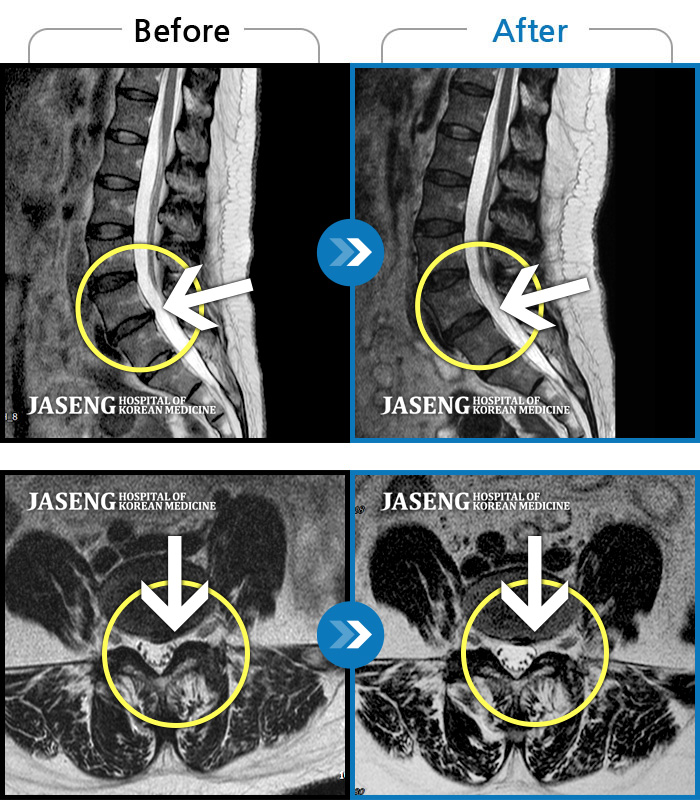

MRI 치료사례

처음 내원 시 허리와 다리 통증이 심한 상태로 내원하셨습니다.